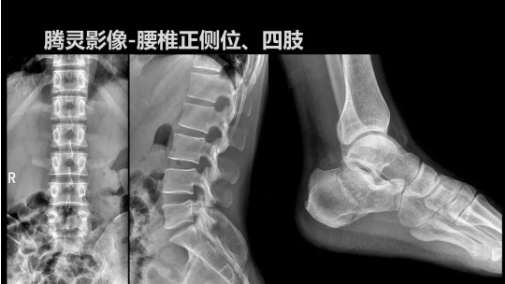

相較前代產(chǎn)品,“騰靈”在圖像質(zhì)量方面得到了全面升級,“騰靈”采用17*17非晶硅平板探測器設(shè)計(jì),采集矩陣達(dá)3072*3072,動(dòng)態(tài)范圍達(dá)16bit,為成像提供超大視野的同時(shí)保證成像質(zhì)量,此外,該款機(jī)型可根據(jù)醫(yī)療機(jī)構(gòu)的差異化需求而選配不同的動(dòng)態(tài)平板探測器,以此來適應(yīng)不同階層用戶所需。